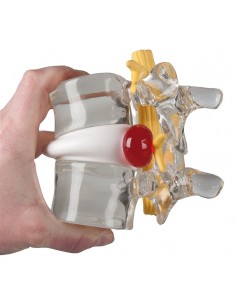

Modello su cavalletto rimovibile di 2 vertebre lombari con nervi spinali; 2 dischi intervertebrali sostituibili con un ernia al disco mediale.

Modello scomponibile nei suoi elementi (corpo vertebrale, dischi e nervi del midollo spinale)

Una sorprendente presentazione didattica per l'osteoporosi, con un confronto tra vertebre toraciche osteoporotiche e sane.